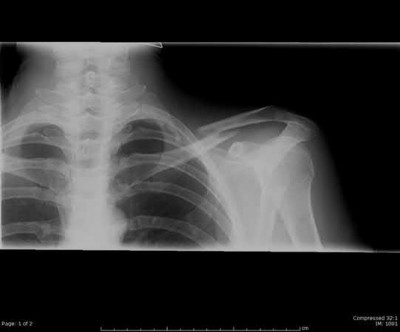

A 44-year-old male is struck by a vehicle while riding his bike. In the trauma bay, he complains of right shoulder pain . Upper extremity physical exam reveals no neurologic deficits, and an initial radiograph of the shoulder is shown in Figure A. A CT scan of the shoulder shows 1cm of posterior displacement of the tuberosity fragment. Which of the following is true regarding this injury?

The radiograph in Figure A demonstrates a posteriorly displaced greater tuberosity fracture. These injuries are often associated with anterior shoulder dislocations, and concomitant rotator cuff tears. The subscapularis attaches to the lesser tuberosity, and is not a deforming force. Open reduction and internal fixation (ORIF) is usually the treatment of choice, and it is well accepted that more than 5mm of displacement is an indication for surgery in patients that require overhead function of the arm.

Flatow et al evaluated 12 patients who were an average of five years status post ORIF of displaced greater tuberosity fractures. All fractures healed without postoperative displacement. Six patients had an excellent result and six had a good result.

Platzer et al retrospectively analyzed functional and radiographic results of 52 patients with operative treatment of displaced greater tuberosity fractures at an average time of 5.5 years from surgery compared to 9 patients with equivalent injuries treated non-operatively. Evaluation of the results of the surgical study group and the nonoperative control group, patients with reduction and fixat ion of greater tuberosity fractures had significantly better

results on shoulder function than did those with conservative treatment.